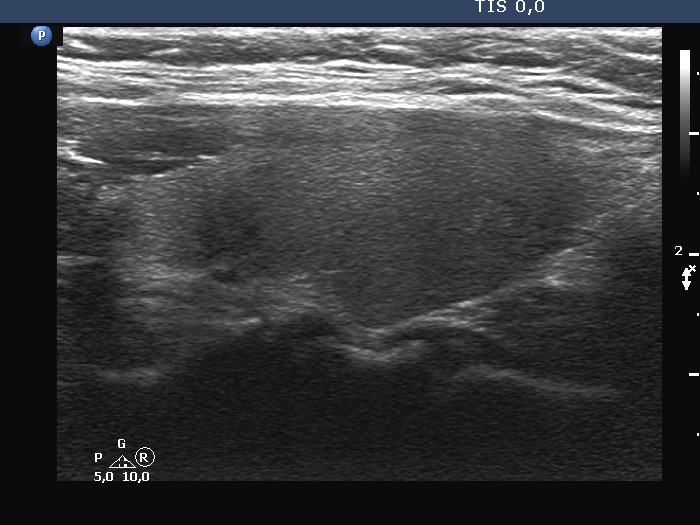

The shape of the nodule - case 1257 (ultrasonographic picture 6)

Left lobe, longitudinal view. The hypoechoic bands are caused by improper fitting of the transducer to the neck of the patient.